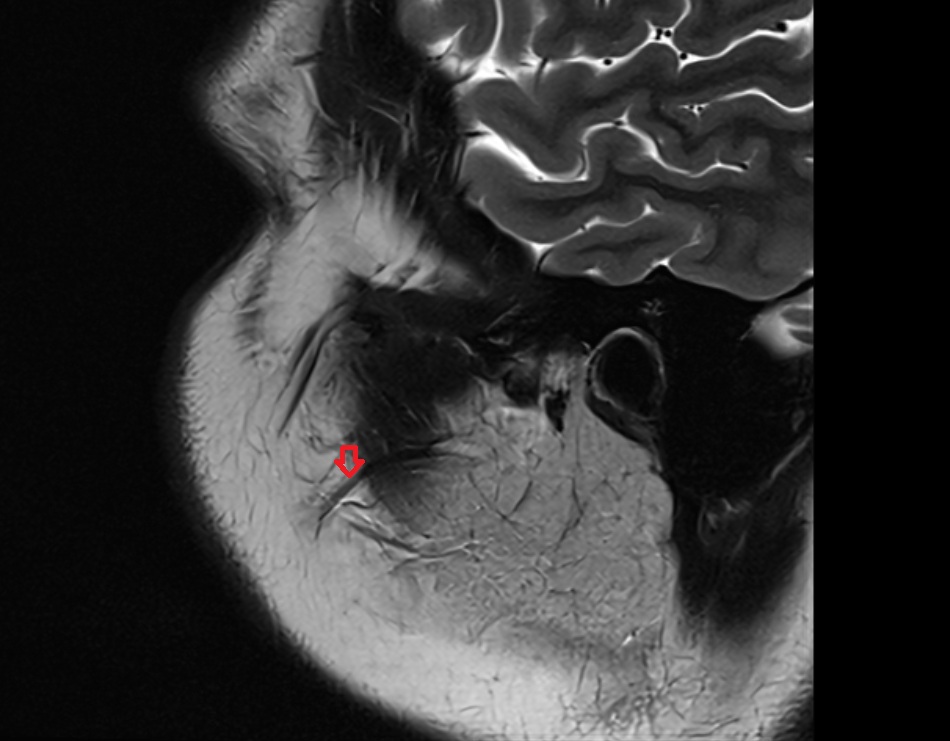

- Head of hippocampus

- Body of hippocampus

- Tail of hippocampus

- Hippocampus

- Dentate gyrus

- Amygdala

- Uncus